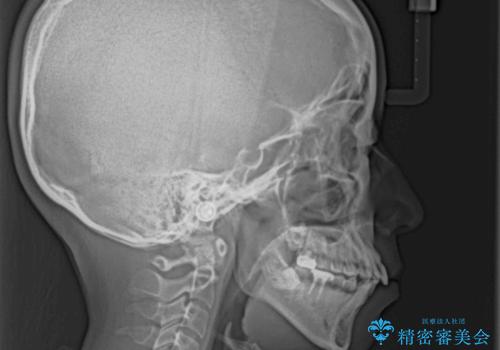

- 前歯のデコボコと口元の突出感を気にして来院された患者様です。

上下前歯がくちばしのように突出していたため、上下左右の第一小臼歯4本を抜歯し、ワイヤー装置にて矯正治療を行うこととしました。

口元の突出感が改善されてことで、下唇に引っかかっていた上顎前歯も気にならなくなりました。